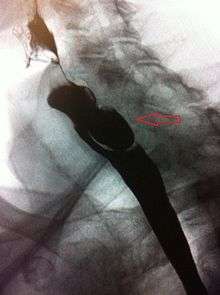

The simple barium swallow will normally reveal the diverticulum. It may also be found with upper GI endoscopy, or CT with oral contrast.

If small and asymptomatic, no treatment is necessary. Larger, symptomatic cases of Zenker's diverticulum have been traditionally treated by neck surgery to resect the diverticulum and incise the cricopharyngeus muscle. However, in recent times non-surgical endoscopic techniques have gained more importance (as they allow for much faster recovery), and the currently preferred treatment is endoscopic stapling[4][5] (i.e. diverticulotomy with staples ). This may be performed through a diverticuloscope. Other methods include fibreoptic diverticular repair.[6]